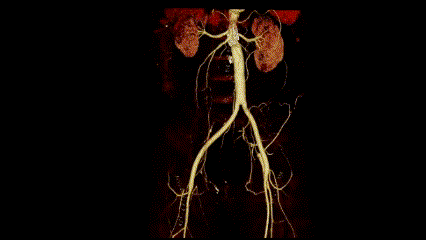

针对刘先生的情况,在张喜成主任的主持下,血管外科与介入科全体医生进行了深入的探讨并制定了2套治疗方案:第一种是介入手术,尽管微创损伤小,但患者存在免疫性疾病,再次介入治疗不仅远期通畅率难保证,仍可能反复闭塞,且费用高昂;第二种是外科开腹人工血管搭桥手术,鉴于患者存在腹膜后纤维化,手术难度大,创伤略大,但远期通畅率会高,且费用较低。将手术方案与刘先生充分沟通后,最终医生们为刘先生实施了主动脉-双侧股动脉的架桥手术。在麻醉科、手术室同仁的大力支持和默契配合下,张喜成主任主刀,孙元副主任医师、黄献琛副主任医师协助,共同为刘先生实施了腹主动脉-双侧股动脉人工血管搭桥术。术中发现患者主动脉与周围组织粘连严重、血管壁脆弱,很难分离,但手术团队凭借过硬的技术,游离出合适的主动脉,去除部分的支架,经过3个半小时的努力,成功完成“架桥”手术。患者安全返回病房,在医护人员的精心治疗与护理下,刘先生恢复迅速,下肢缺血症状完全缓解,复查主动脉CTA,搭桥人工血管血流通畅。

复查主动脉CTA,搭桥人工血管血流通畅。